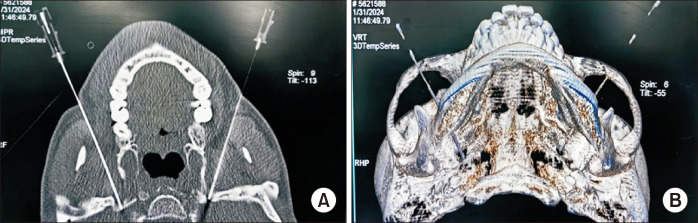

CT-guided extracranial radiofrequency of multiple groups of cranial nerves for the treatment of compound Meige's syndrome.

{"title":"CT-guided extracranial radiofrequency of multiple groups of cranial nerves for the treatment of compound Meige's syndrome.","authors":"Huiling Peng, Chunxiao Wang, Binyue Xin, Bing Huang","doi":"10.3344/kjp.24415","DOIUrl":null,"url":null,"abstract":"","PeriodicalId":56252,"journal":{"name":"Korean Journal of Pain","volume":"38 2","pages":"209-212"},"PeriodicalIF":3.1000,"publicationDate":"2025-04-01","publicationTypes":"Journal Article","fieldsOfStudy":null,"isOpenAccess":false,"openAccessPdf":"https://www.ncbi.nlm.nih.gov/pmc/articles/PMC11965996/pdf/","citationCount":"0","resultStr":null,"platform":"Semanticscholar","paperid":null,"PeriodicalName":"Korean Journal of Pain","FirstCategoryId":"3","ListUrlMain":"https://doi.org/10.3344/kjp.24415","RegionNum":3,"RegionCategory":"医学","ArticlePicture":[],"TitleCN":null,"AbstractTextCN":null,"PMCID":null,"EPubDate":"","PubModel":"","JCR":"Q2","JCRName":"CLINICAL NEUROLOGY","Score":null,"Total":0}